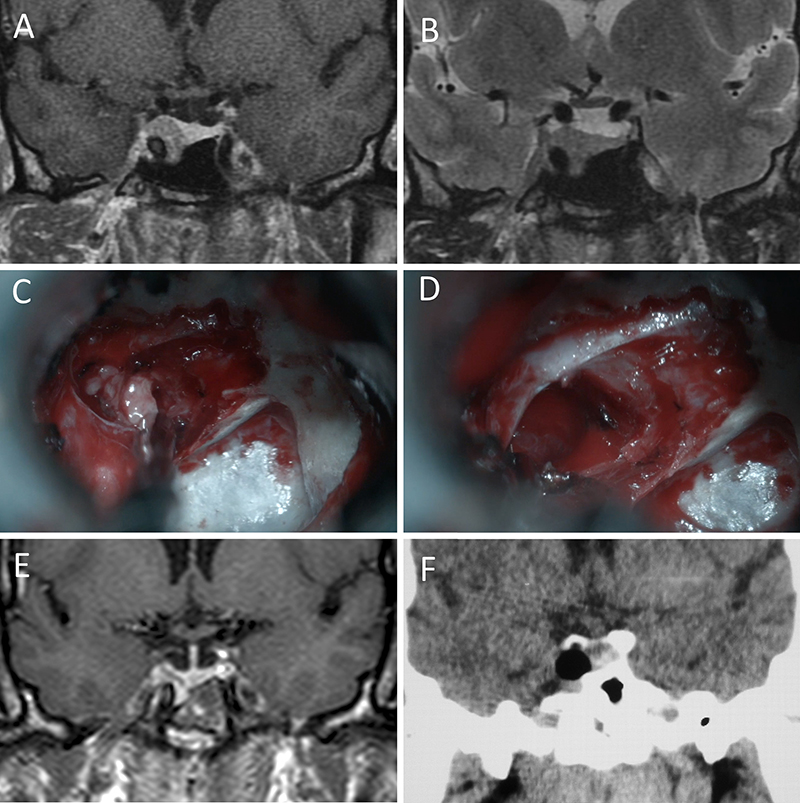

Figura 11: Microadenoma en una mujer de 36 años con Enfermedad de Cushing. Con remisión bioquímica tras la cirugía. A-B: RM preoperatoria; C-D: intraoperatorio; E-F: RM postoperatoria.

Figura 12: Microadenoma en una mujer de 26 años con Enfermedad de Cushing. Con remisión bioquímica tras la cirugía. A-B: RM preoperatoria; C-D: intraoperatorio; E-F: RM postoperatoria.

Figura 13: Macroadenoma en una mujer de 42 años con Enfermedad de Cushing. Con remisión bioquímica tras la cirugía. A-B: RM preoperatoria; C-D: intraoperatorio; E-F: RM postoperatoria.